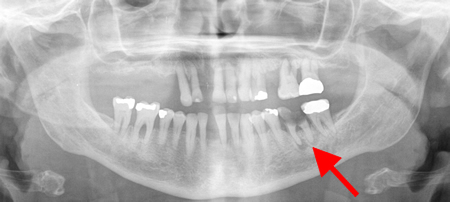

Panoramic radiograph showing generalised advanced horizontal periodontal bone loss with periapical radiolucency (see arrow) related to left mandibular first molar consistent with combined endodontic/periodontal abscess

From the personal collection of Melanie S. Lang and Thomas B. Dodson; used with permission